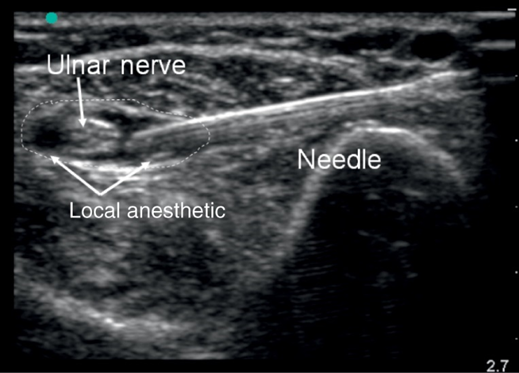

Loco-regional anesthesia works by injecting local anesthetic agents near specific nerves or into the regional spaces of the body. This prevents nerve signals from reaching the brain, effectively blocking pain in the targeted area. The patient remains conscious but does not feel pain in the anesthetized region.

– Injection: The anesthesiologist will inject the local anesthetic near the targeted nerves or into the appropriate space using an ultrasound machine.